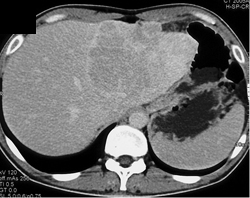

Hepatoma- Multifocal